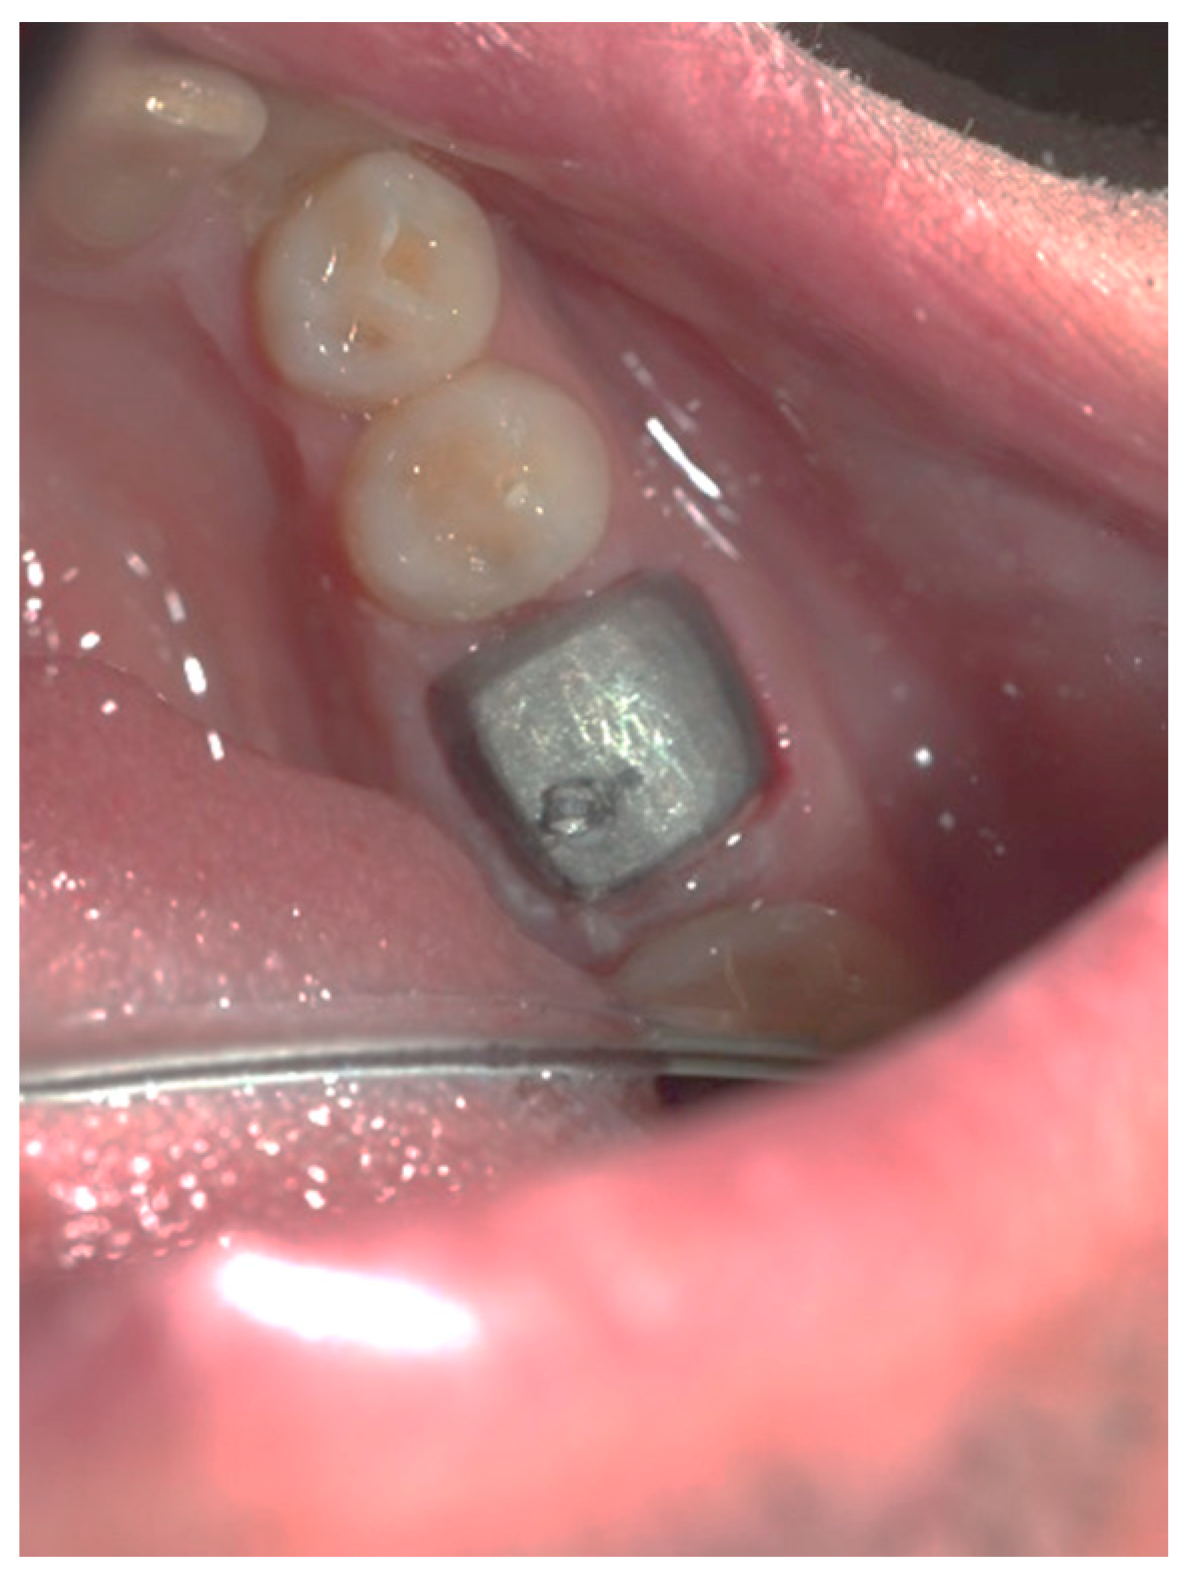

Figure 3, Figure 4, Figure 5, Figure 6, Figure 7 and Figure 8 display the follow-up of the healing process after a resective procedure for lengthening a short clinical crown with a laser.

Figure 8.

The cemented permanent metal–ceramic crown.